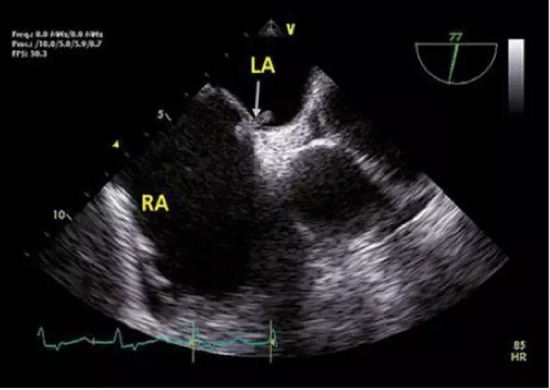

列位看官,你们肯定忽视了一种心脏疾病所致的偏头痛:卵圆孔未闭。

卵圆孔其实是心房原发隔与继发隔之间的一个缝隙。由于这个解剖结构的存在,当情绪激动等其他原因导致胸腔内压力过高时,可能会导致心房之间出现右向左的分流。因静脉血中化学物质如 5-羟色胺等血管活性物质较多,在分流后会导致脑血管扩张出现偏头痛。

所以在临床中会有一些不明原因偏头痛的患者,能够卵圆孔未闭封堵中获益。

卵圆孔未闭,一般是左向右分流,在右心压力升高时,可出现右向左分流

卵圆孔处的骑跨血栓

除功能性头痛,卵圆孔未闭更大的潜在风险,是导致矛盾栓塞。即来自下肢深静脉或右心系统的血栓,通过卵圆孔进入左心系统,继而导致外周动脉尤其是脑血管栓塞。